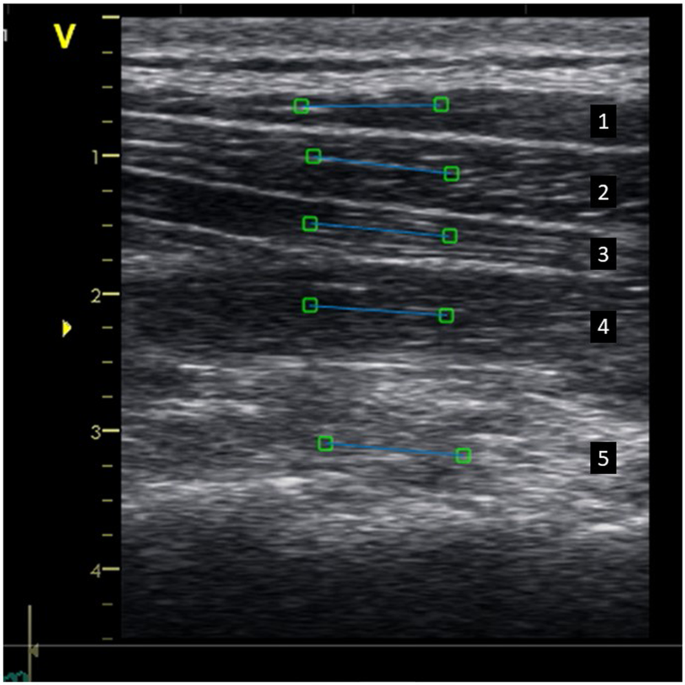

Ultrasound of muscle results in reflection of soundwaves, which serve as acoustic markers because they form a unique speckle pattern. A gray-scale image on muscles is composed of several bright speckles, due to small irregularities in the muscles. This acoustic marker, speckle pattern, is unique and remains relatively stable over time, and can therefore be followed frame-by-frame in a sequence of images37. To track the unique speckle pattern in the neck muscles, a region of interest (ROI) was manually selected in each of the five muscles (Fig. 10).

Ultrasound image of the dorsal neck muscles with Region of Interest (ROIs). Muscles are arranged in layers (from top to bottom): (1) trapezius, (2) splenius, (3) semispinalis capitis, (4) semispinalis cervicis, and (5) multifidus/rotatores. Five regions of interest (ROIs; each indicated as a blue line with a square on each end) were selected in each muscle for post-process speckle tracking analysis.